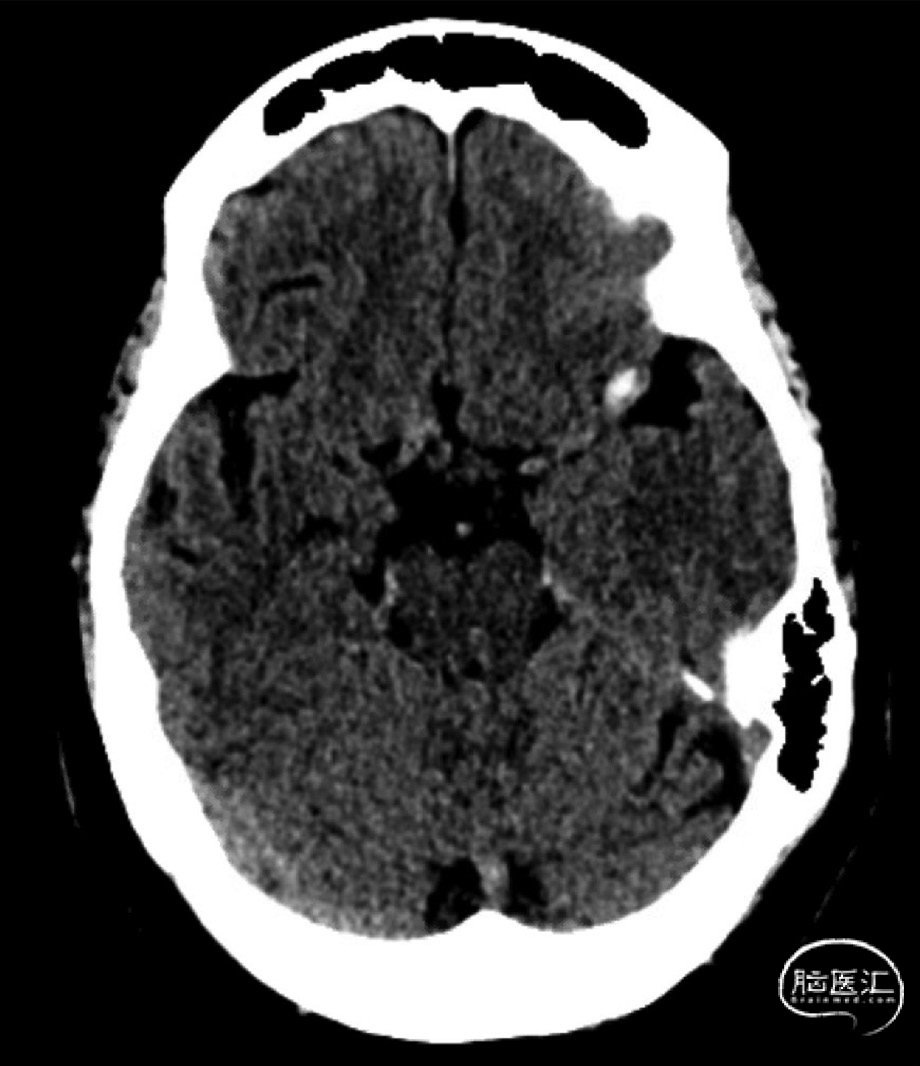

平扫CT(图1)可见MCA局部高密度信号为动脉瘤内血栓形成: